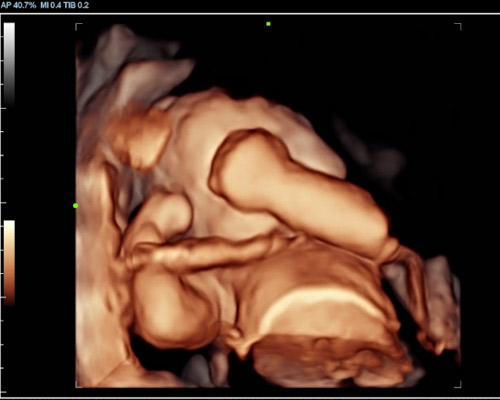

A 3D/4D bonding scan combined with a heartbeat bear near Wakefield offers a unique way to experience both visual and emotional connection before birth.

A 3D scan captures detailed still images of your baby’s face and body, while a 4D baby scan Wakefield allows you to see those images in motion. You may notice movements such as stretching, turning, or subtle expressions, making the experience feel more real.

With a 4D baby ultrasound Wakefield, this technology allows you to see your baby with greater clarity and depth. The result is softer, more lifelike visuals that can feel closer to a photograph than a traditional scan.

Our Scans